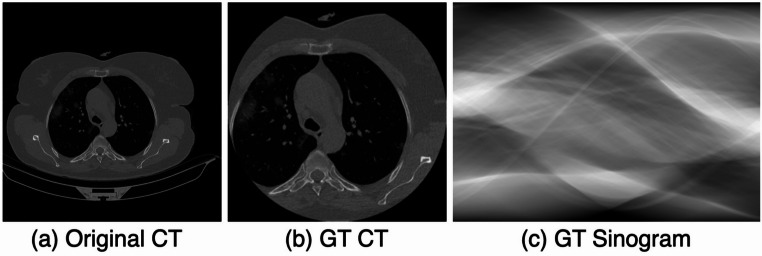

This study proposes a deep learning-based diagnostic model called the Projection-wise Masked Autoencoder (ProMAE) for rapid and accurate COVID-19 diagnosis using sparse-view CT images. ProMAE employs a column-wise masking strategy during pre-training to effectively learn critical diagnostic features from sinograms, even under extremely sparse conditions. The trained ProMAE can directly classify sparse-view sinograms without requiring CT image reconstruction. Experiments on sparse-view data with 50%, 75%, 85%, 95%, and 99% sparsity show that ProMAE achieves a diagnostic accuracy of over 95% at all sparsity levels and, in particular, outperforms ResNet, ConvNeXt, and conventional MAE models in COVID-19 diagnosis in environments with 85% or higher sparsity. This capability is especially advantageous for the development of portable and flexible imaging systems during large-scale outbreaks such as COVID-19, as it ensures accurate diagnosis while minimizing radiation exposure, making it a vital tool in resource-limited and high-demand settings.

Abstract Image